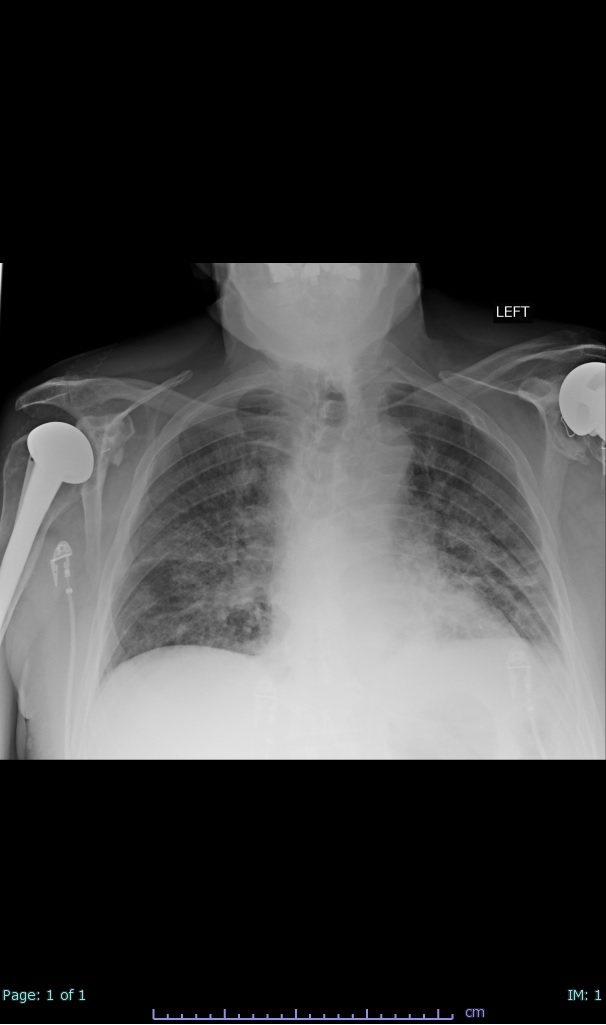

- 66% had some + CXR finding I could correlate to a CT finding

- 66% had documented exposure, rest I couldn't find either way